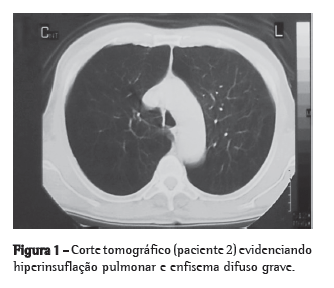

Foram admitidos neste estudo os doentes que obedeceram aos critérios de inclusão e exclusão. Os critérios de inclusão foram os seguintes: pacientes diagnosticados com enfisema, com radiografia de tórax em inspiração e expiração e tomografia de tórax de alta resolução evidenciando enfisema difuso homogêneo ou heterogêneo mostrando hiperinsuflação pulmonar (Figura 1); idade de até 75 anos; presença de invalidez apesar do tratamento clínico máximo (reabilitação pulmonar) por no mínimo 6 meses; VEF1 após broncodilatador < 30% do predito; volume residual maior ou igual a 150% do predito; capacidade pulmonar total maior do que 100% do predito; cessação do tabagismo no mínimo 6 meses antes do procedimento; e pacientes candidatos ao transplante pulmonar ou a operação redutora de volume pulmonar.